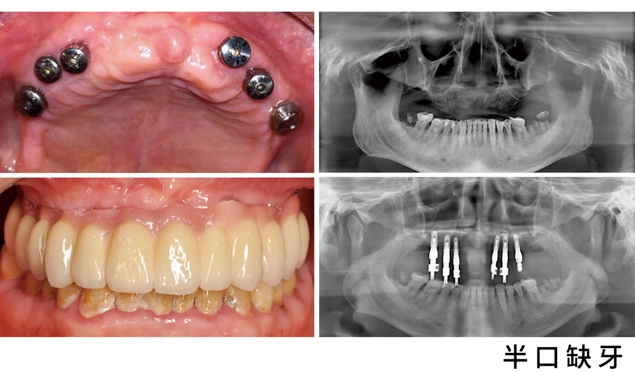

半口全固定种植牙

半口种植牙示意图

昆明美奥口腔半口种植牙案例